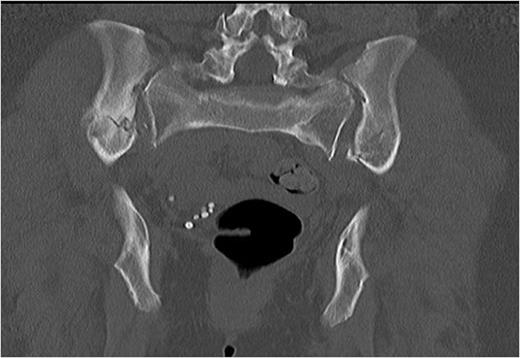

A 57 year old woman slipped while shopping resulting in a fall, where-upon her right hip flexed to 90 degrees and her left hip extended to 90 degrees, to a point where her perineum came to rest on the floor. This particular fall resulted in a twisting or torque like force being transmitted through her pelvis as she fell. She was helped up after the fall and was able to mobilise with assistance. She attributed the increased pain that she was experiencing to aggravation of her long standing back complaint. Prior to her fall she had attended the spinal clinic for her back pain and was scheduled for a bone scan with a view to progressing to facet joint blocks. On attendance at the spinal clinic following her scan it was noted that her low back pain had become more pronounced and she required walking aides in the form of crutches to mobilise. On reviewing the bone scan, multiple areas of increased uptake were noted in the bony pelvis. Further imaging, both plain film and computed tomography (CT) (Fig.1 & Fig. 2) revealed extensive pelvic fractures with displaced bilateral superior and inferior pubic rami fractures and bilateral posterior ring crescent fractures. Her past medical history was significant only for her aforementioned back pain. She had no previous fractures and prior to her fall worked as a care assistant.

Coronal computerised tomography (CT) image demonstrating bilateral posterior iliac wing fractures and sacro-iliac joint disruption